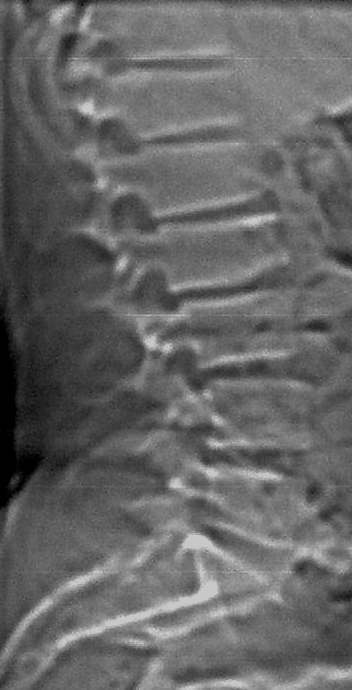

青年性驼背,该病主要发生于椎间软骨。好发于12-18岁,当过度负重时,在椎间盘的先天性薄弱处将发生琗裂,髓核疝入,形成许莫氏结节。本例见髓核疝入l2椎体前下缘的典型表现,且见椎间盘真空征。

定位像显示l2椎体下缘前部局限性凹陷性改变,局部骨皮质硬化,未见明显骨质破坏,各椎间隙略变窄. ct横断扫描显示椎体前缘不光整,呈退行性改变表现,未见骨质破坏,软组织肿块等异常,双侧腰大肌正常.

考虑:腰椎及椎间盘退行性改变(l2前缘系许莫氏结节+扫描层面与椎体下缘不平行所致).